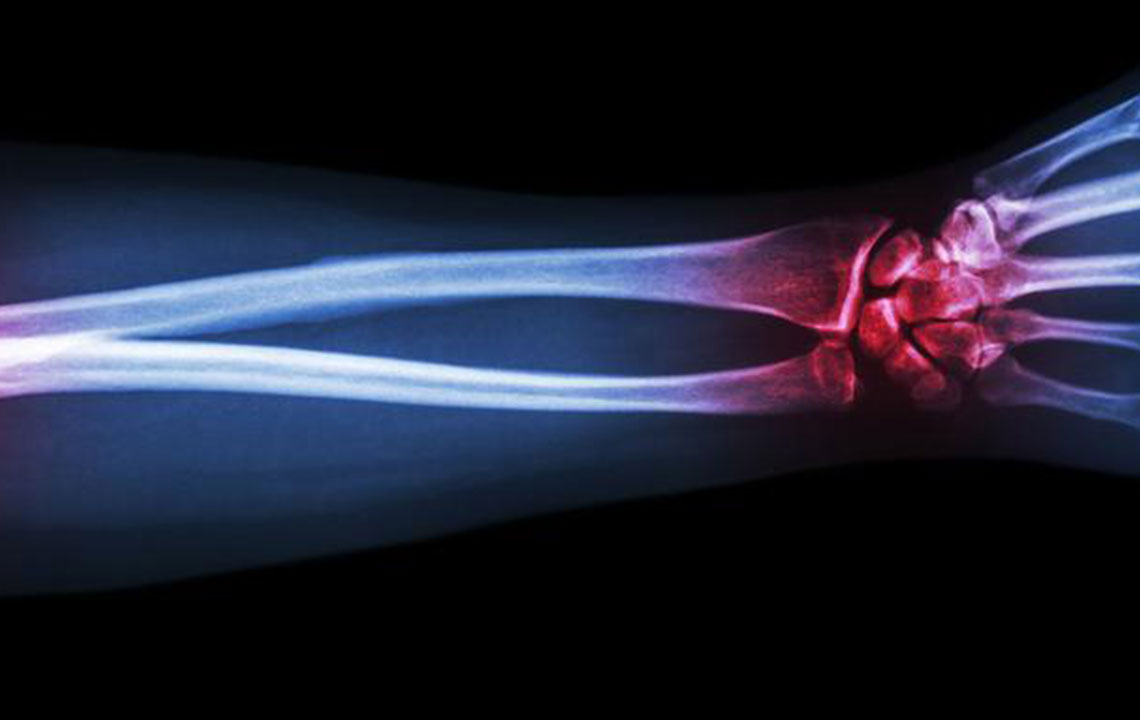

Gout is a type of arthritis that primarily attacks the joints and other body parts like the ears, wrists, knuckles, knee, ankles, and other small joints. It is often characterized by painful swelling, stiffness, and inflammation of these affected joints. The swelling and stiffness are mainly the results of excess levels of uric acid forming crystals in the joints.